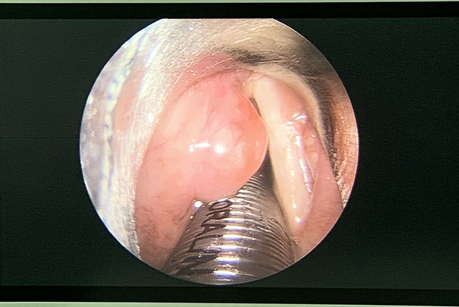

术中左侧喉室中段见肿物,约1.0cm*1.0cm,表面光滑、充血,紧贴左侧声带